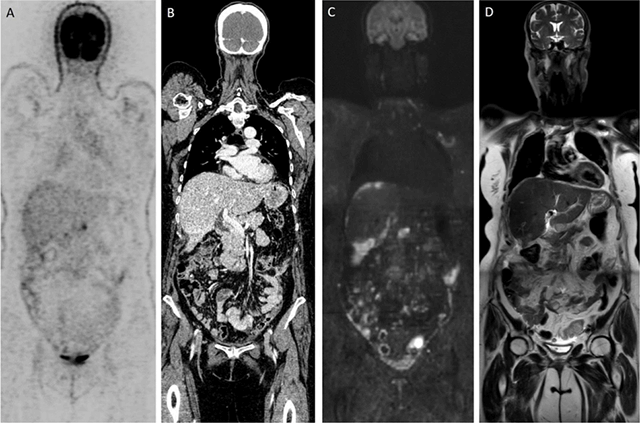

Figure 1

Patient with diagnosis of ovarian cancer: (A, B) Time-of-flight FDG-PET/CT depicts limited number of peritoneal metastases. (C, D) Contrary, WB-DWI/MRI shows diffuse nodular and confluent carcinomatosis visible as b1000 hyperintense lesions on the (C) DWI-image.